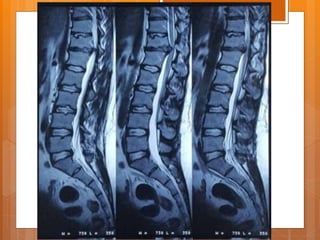

Case presentation  Female 21 y/o  Back pain from 1.5 years ago  Exacerbated after child delivery (9m ago)  Pain radiated to right leg from 7m ago

P/E  ↓L3 ,L4 force  right clonus  ↓ achilles DTR  QC DTR normal  Babinski sign normal  Intermittent Bladder dysfunction  Sensory normal